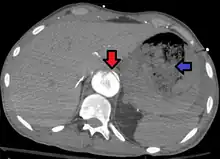

| Aorto enteric fistula and aortic dissection of the thoracic aorta. Arrow shows the flap in the aorta. Heterogeneity is blood in the stomach |